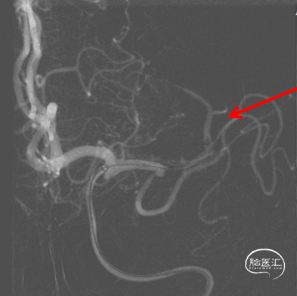

管壁毛糙,泵替罗非班观察15分钟(60Kg,静脉推注7ml后7ml/h微泵维持)。

CT良好

15分钟后“打回原形”

1、原位血栓?→替罗非班已泵

2、ICAS闭塞?

3、夹层含壁间血肿成分再次闭塞?